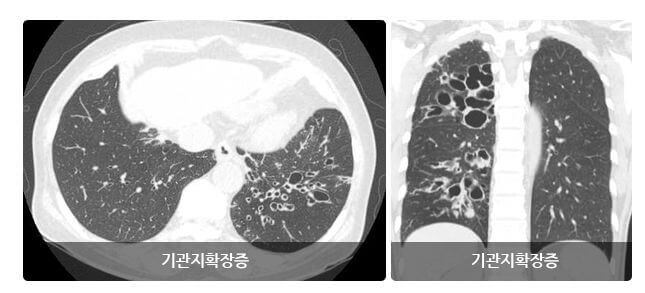

기관지확장증은 폐 속의 큰 기도인 기관지가 과거의 심한 호흡기계의 염증으로 기관지가 비정상적으로 늘어나 여러 가지 문제를 일으키는 질환을 말합니다.

확장된 기관지 내부에는 가래가 고이게 되는데 기관지가 손상되어 있는 상황이므로 잘 빠져나가지 못하게 되고 이로 인해 쉽게 감염되고 그러면서 기관지 벽이 약해집니다.

이렇게 되면 기관지가 쉽게 파괴되고 다시 가래가 증가되는 악순환이 형성됩니다.